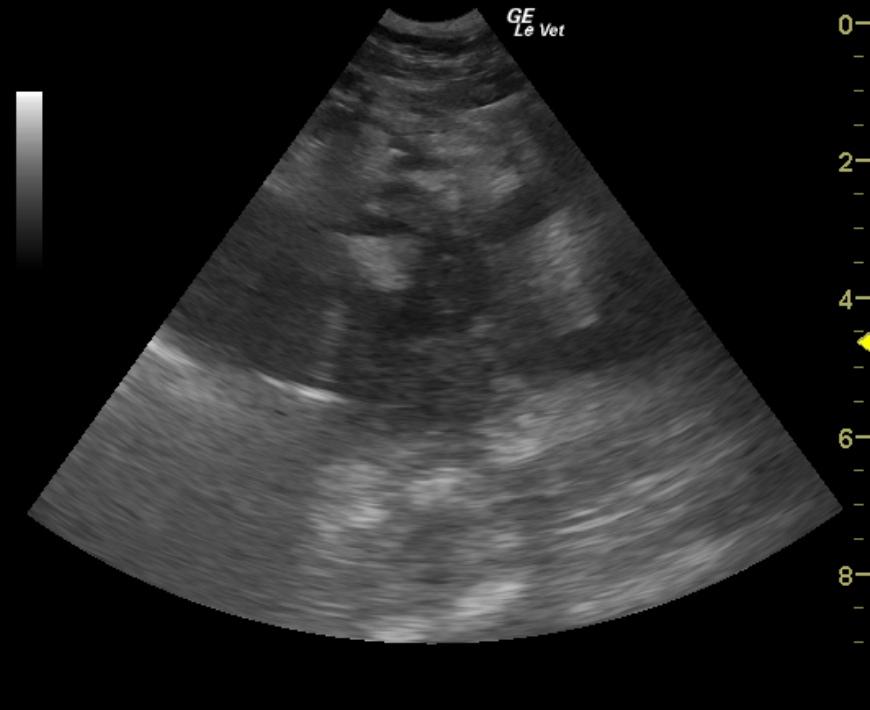

A 4-year-old MN DSH was presented for being not himself lately. Abnormalities on physical examination were increased respiratory effort and bilateral muffled heart sounds on auscultation. CBC, blood chemistry, and FeLV/FIV assay were all within normal limits. Thoracic radiographs showed pleural effusion with opacification of the heart. Approximately 80mls of turbid, hemorrhagic fluid was aspirated from both sides of the thorax, which on analysis was found to be an exudate. The patient was treated with Lasix and ampicillin.